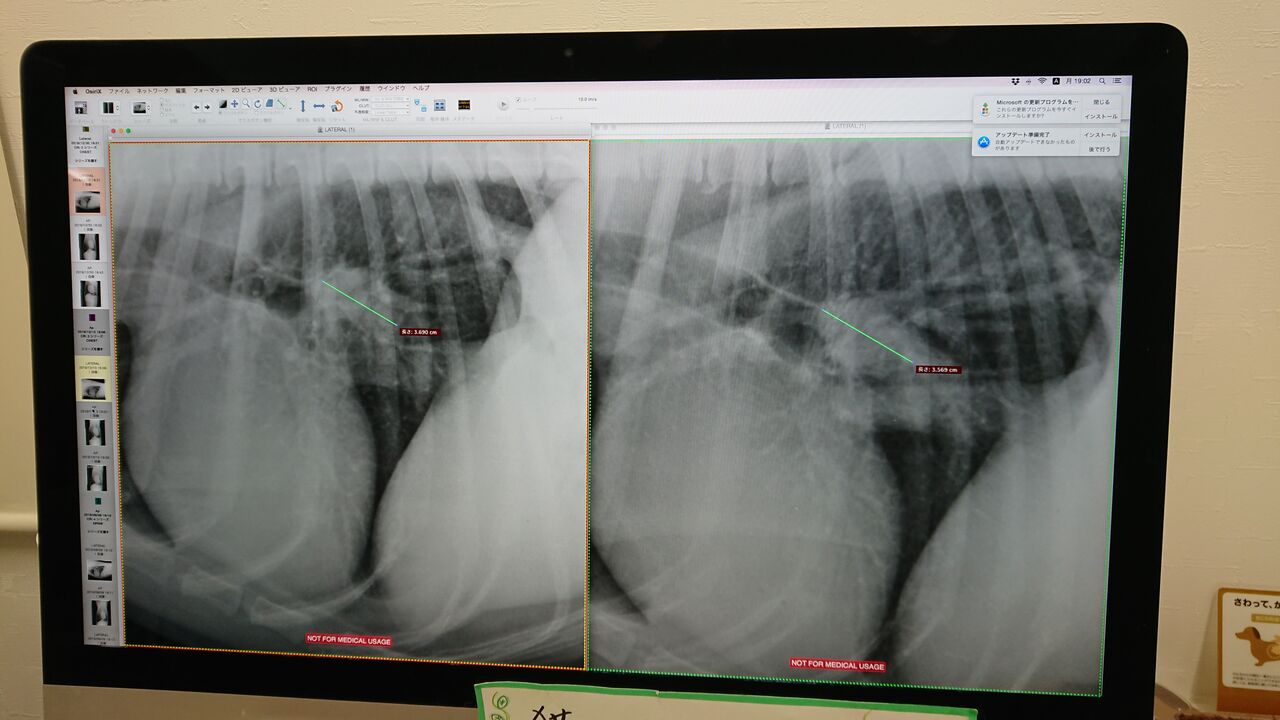

¥ì¥ó¥È¥²¥ó¡£º¸Â¦¤Ï12·î30Æü¡£±¦Â¦¤¬12·î13Æü¡£

Â礤µ¤ÏÊѤï¤é¤º¡£

¿Ê¹ÔÅٹ礤¤¬¤ï¤«¤é¤Ê¤¤¤Î¤Ç¡¢º£¤ÎÃʳ¬¤Ç¤Ïɾ²Á½ÐÍè¤Þ¤»¤ó¤¬¡¢Â礤¯¤Ê¤Ã¤Æ¤Ê¤±¤ì¤ÐÂç¾æÉס£

¥ì¥ó¥È¥²¥ó²èÁü¤Ç¤Ï¼ðáç¤ÏÉÔÁ¯ÌÀ¤Ê¤Î¤Ç¡¢¤¢¤ëÄøÅÙ¤ÎÃʳ¬¤ÇCT²èÁü¤Ç¤Îɾ²Á¤¬É¬ÍפˤϤʤê¤Þ¤¹¡£